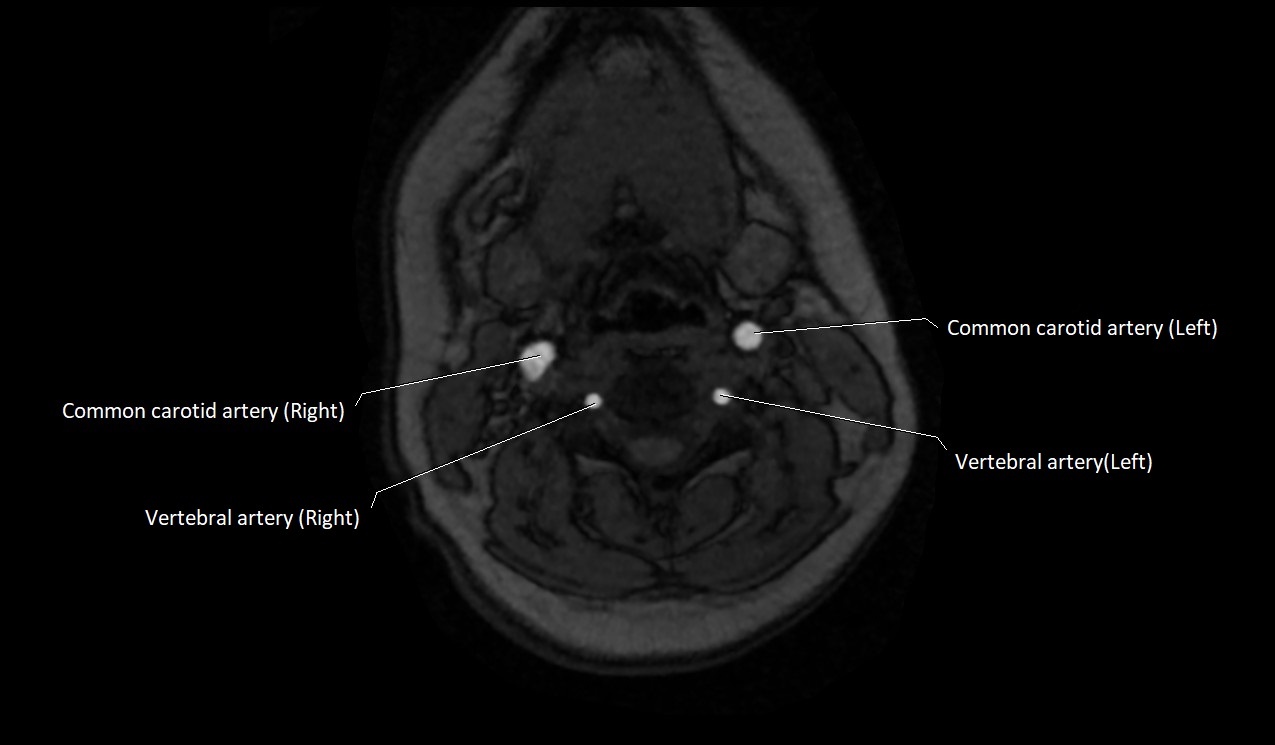

MRI Appearance:

• T1-Weighted Images:

• Appears as a tubular, hypointense (dark) structure relative to muscle

• May show flow void if the blood flow is fast

• T2-Weighted Images:

• Typically hypointense or isointense to muscle, but can be hyperintense if slow flow or stasis is present

MRI images